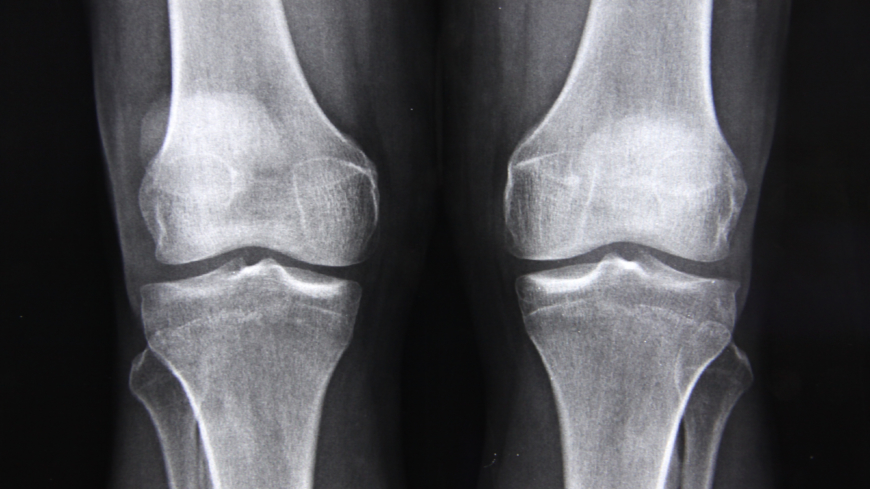

Osteoporos, även kallat benskörhet, och där till kopplade osteoporosfrakturer, är en av de vanligaste svenska folksjukdomarna och som drabbar varannan kvinna över 50 år. Vid osteoporos blir skelettet skört och kan lätt brytas, det kan i de svåraste fallen räcka med en hostning. Det finns verkningsfull behandling men långt ifrån alla kvinnor får ta del av denna behandling.

Benskörhet drabbar i första hand äldre kvinnor men förekommer även hos yngre kvinnor och hos män. Håkan Sinclair, geriatriker och överläkare vid Borås lasarett ger oss det vi behöver veta om en av Sveriges största folksjukdomar.

Med över 200 ben i vår kropp är kunskap om vad benskörhet (Osteoporos) är och hur det behandlas, och hur du själv kan förebygga sjukdomen, viktig.

Benskörhet är en vanlig åkomma hos kvinnor efter klimakteriet. Många drabbas av skelettskador med smärta, funktionshinder och nedsatt livskvalitet som följd. Värst är frakturer på ryggkotor som ger ett mycket långvarigt lidande, visar en doktorsavhandling vid Linköpings universitet.